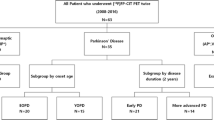

This prospective study, which was conducted at a single, tertiary academic center, was approved by the Asan Medical Center institutional review board (2018-0183), and all patients signed an informed consent form. Between April 2018 and October 2018, 15 patients with probable ET (13 females and 2 males; mean age ± standard deviation (SD), 68.9 ± 6.6 years) and 10 patients with PD (4 females and 6 males; mean age ± SD, 70.5 ± 6.3 years; Hoehn and Yahr (H&Y) stage 2.3 ± 0.8) were enrolled. The diagnoses of ET and PD were based on the Consensus Statement of the Movement Disorder Society on Tremor [14] and the UK Parkinson’s Disease Society Brain Bank Clinical Diagnostic Criteria [15], respectively. The following exclusion criteria were applied: (a) hypersensitivity or allergy to [18F]FP-CIT; (b) history of alcohol or drug abuse; (c) history of stereotactic surgery; and (d) the use of cocaine, benztropine, amphetamines, phentermine, mazindol, and methylphenidate. Each subject underwent two sequential [18F]FP-CIT PET/CT scans at an interval of 48 ± 7 day. All subjects performed MR scans (average time interval between MRI and test PET was 44 ± 14 days).